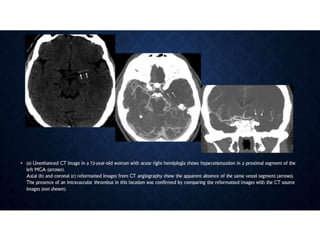

• • Is there hemorrhage that explains the symptoms or excludes lytic

• • Is there intravascular thrombus that can be targeted for thrombolysis?